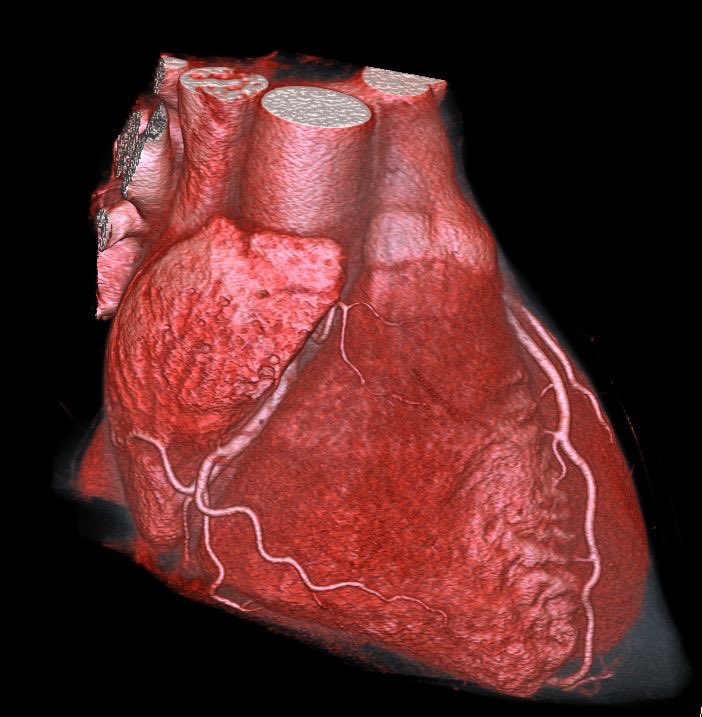

Hypertrophic cardiomyopathy (HOCM) on cardiac CT #cardiotwitter @escardio @M_Ijgua @M_Marwan_ @CardiacCTGuy @Heart_SCCT @FiRSTSCCT @Drroxmehran @mirvatalasnag @HolgerNef @BudoffMd @mgwfriedrich @BayerMatthias @JEscaned @thiele_holger @YoungDgk

2

12

56